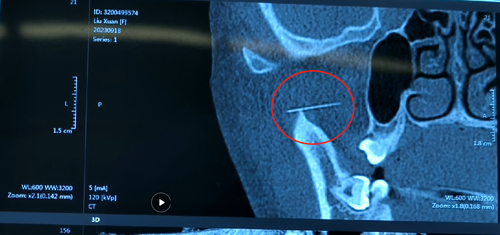

术前影像,红圈内为断针

“当时针灸完,拔针的时候发现,针断了,半截针在孩子脸里”,笑笑母亲说到,“当时就赶紧去了我们当地医院,拍了片,医生给我说太小,取不了,让我们去上级医院。”

9月20日上午,笑笑推进了手术室,一场与断针的较量开始了,首先通过天玑骨科机器人不断的精准定位,规划路径,3D立体成像,确定了断针位置和手术位置,在谢书强副院长和吴召森副院长带领下,数位医生开始为笑笑进行手术。

“过程还是比较艰难的,断针太小了,无疑是大海捞针,幸亏我们使用了最新的机器人,定位非常准确,省去了摸索断针位置和深度的阶段”,吴召森副院长说到,“这个手术有三大难点,第一,面部神经、血管非常丰富,操作起来需要非常小心,第二,断针会随着手术刀移动,变换位置,也许刚才确定的位置,断针已经不在那了,第三,患者比较年轻,希望伤口比较小。”